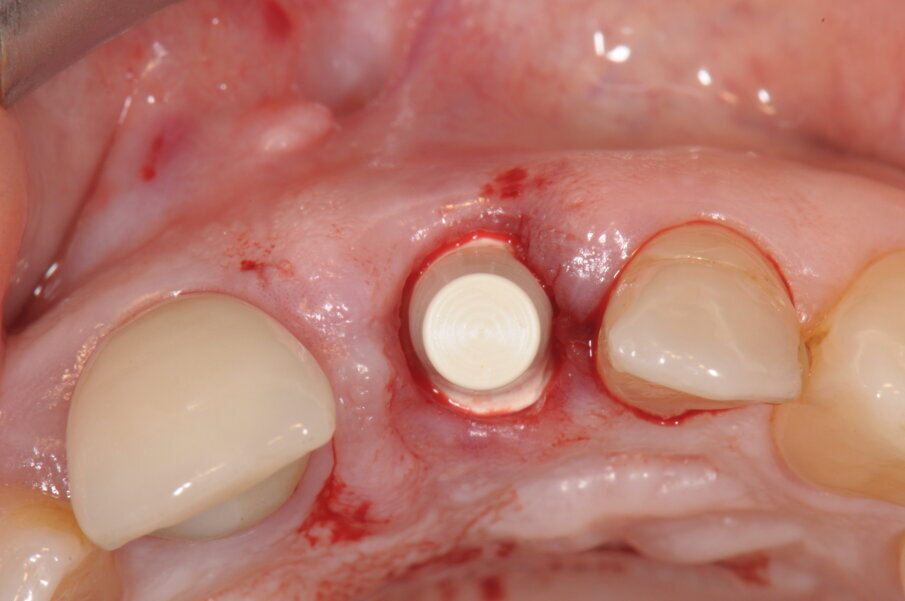

L’utilizzo di un impianto in ceramica prevede le stesse procedure chirurgiche usate per gli impianti convenzionali in titanio, nello specifico impiego di impianti Monotype, cioè a corpo unico col moncone, esistono degli analoghi chirurgici che determinano l’altezza del moncone che si vuole adottare. Nel caso specifico la procedura chirurgica si è basa sulla diagnosi radiografica endorale e sulla visione clinica dell’alveolo successiva all’estrazione, cercando di posizionare l’impianto nella parte mesio-palatale dell’alveolo e cerando di impattare l’apice dell’impianto nella porzione ossea sovrastante l’apice radicolare. Ovviamente la posizione deve anche tener conto di un’adeguata inclinazione rispetto alla futura corona protesica, alla distanza inter-arcata con la porzione apicale del moncone e al rispetto delle papille limitrofe (Fig. 4). A preparazione impostata andiamo a scegliere tra 2 diverse altezze di moncone (4 mm o 5.5 mm) (Fig. 5). L’impianto è custodito in un’apposito sostegno sagomato in cui si trova anche il mounter utilizzabile per un’inserimento manuale o a manipolo (Fig. 6). Sul mounter è disegnata una linea con 3 punti verticali che identificano ciascuna delle 4 facce piane del moncone implantare e la distanza tra loro consente di stabilire nella fase di posizionamento la profondità a cui si pone l’impianto (Fig. 7). Nel posizionare l’impianto si devono compiere 2 scelte coincidenti, la prima dove collocarsi con la porzione del collocare dell’impianto e conseguentemente quanto approfondire la connessione protesica, mentre la seconda è legata all’altezza del moncone. Nello specifico abbiamo voluto dare una maggior estetica approfondendo una parte del collarino, pur utilizzando un moncone di 5.5 mm che ci garantirà un’ottima stabilità protesica. La rx endorale a fine intervento stabilisce il corretto posizionamento, prima di proseguire con la realizzazione della corona provvisoria.

Fig. 5 - A preparazione del sito impiantare ultimata abbiamo inserito un analogo dell’impianto per stabilire l’altezza del moncone da utilizzare.

Fig. 7 - Impianto posizionato, visione del moncone e sua corretta posizione.